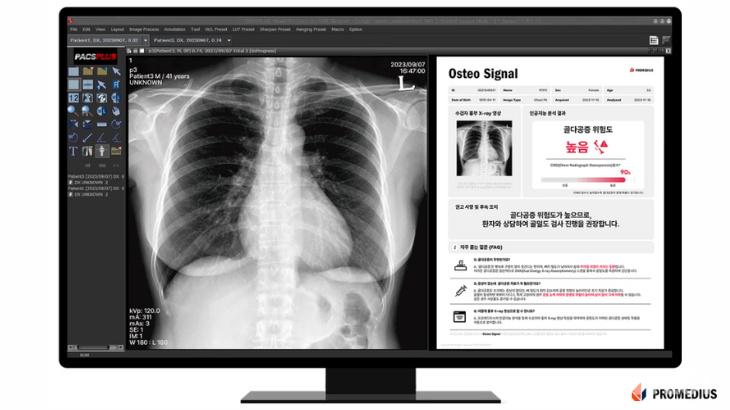

③ 프로메디우스: 노화 및 대사질환 AI 플랫폼으로 건강한 노화 실현

노화 및 대사질환 AI 기술 개발 스타트업 프로메디우스(대표 배현진)는 우리벤처파트너스의 추천을 받아 스케일업 팁스에 최종 선정됐다.

프로메디우스는 향후 3년간 총 11억 4,000만 원 규모의 연구개발비를 지원받아 서울아산병원과 공동으로 '흉부 X-ray 파운데이션 모델 기반 노화·대사질환 예측 및 모니터링 AI 플랫폼'을 개발할 예정이다. 이 플랫폼은 AI가 흉부 X-ray 영상 데이터를 분석해 골다공증, 관상동맥 석회화 지수, 생체 나이 등 주요 노화 지표를 예측하고, 질환 진행을 모니터링하는 의료용 솔루션이다.

구체적으로 회사는 팁스 과제를 통해 기존 골다공증 선별 AI 기술을 심혈관 질환과 생체 나이 평가 영역으로 확장하고, 관련 기술 상용화를 추진한다. 국내외 인허가(MFDS, FDA, CE), 지식재산권 확보, 임상 검증 등을 거쳐 글로벌 시장 진출도 본격화할 방침이다.

배현진 프로메디우스 대표는 "이번 R&D를 통해 건강한 나이듦을 지원하는 차세대 의료 AI 플랫폼을 완성하고, 국내를 넘어 글로벌 헬스케어 시장에서 경쟁력을 확보해 나갈 것"이라며 "증상이 없는 고위험군을 조기에 식별하기 어려운 기존 검진 체계의 한계를 극복해 초고령 사회의 주요 보건 이슈인 '노화 및 대사질환' 해결에 기여하겠다"라고 포부를 밝혔다.